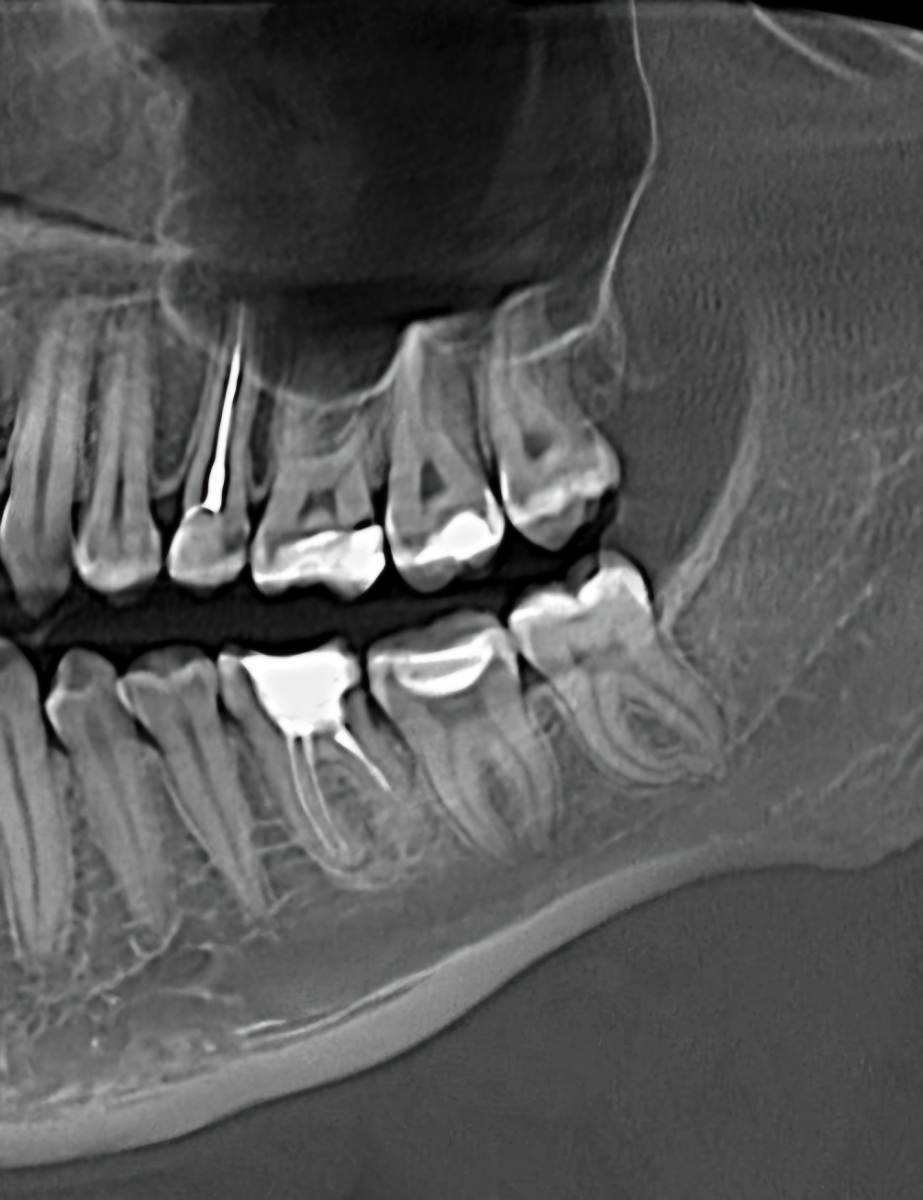

Л93 Опубликовано Понедельник в 18:57 Поделиться Опубликовано Понедельник в 18:57 (изменено) Доброго времени суток. Очень нужна консультация. В субботу припухла щека, заболела верхняя челюсть, конкретное место определить не удалось. Сегодня на осмотре у стоматолога вердикт, удалять 8ку и 5ку. Пошла на удаление, хирург внимательно изучив снимки, посоветовавшись с коллегой сказал, что 5ка под лечение, 8ка ещё и не вышла и с ней все в порядке. Прописал антибиотик и отправил к терапевту. Ближайшая запись к терапевту май. Действительно ли можно обойтись без удалении 5ки? Как срочно нужно заняться лечением если возможно вылечить 5ку? Заранее спасибо всем ответившим. Изменено Понедельник в 18:59 пользователем Л93 Ссылка на комментарий

Женька Опубликовано Понедельник в 19:36 Поделиться Опубликовано Понедельник в 19:36 Здравствуйте! Криминала не вижу по Вашему 25 зубу. Но это лишь один срез, не дающий полной картины. По 8... интересно посмотреть в полости рта. Потому что на снимке 6 лет назад она действительно не прорезалась, а вот на свежем вполне себе должна жевать с нижней 8. Ссылка на комментарий

Л93 Опубликовано Вторник в 09:59 Автор Поделиться Опубликовано Вторник в 09:59 @red_butler вчерашний снимок кт в первом сообщении Ссылка на комментарий

wladdX Опубликовано Вторник в 21:40 Поделиться Опубликовано Вторник в 21:40 (изменено) Скорее всего виновен 25 Изменено Вторник в 21:41 пользователем wladdX Ссылка на комментарий

red_butler Опубликовано 16 часов назад Поделиться Опубликовано 16 часов назад Здравствуйте, требуется повторное лечение корневых каналов пятого зуба. почитайте эту тему Ссылка на комментарий